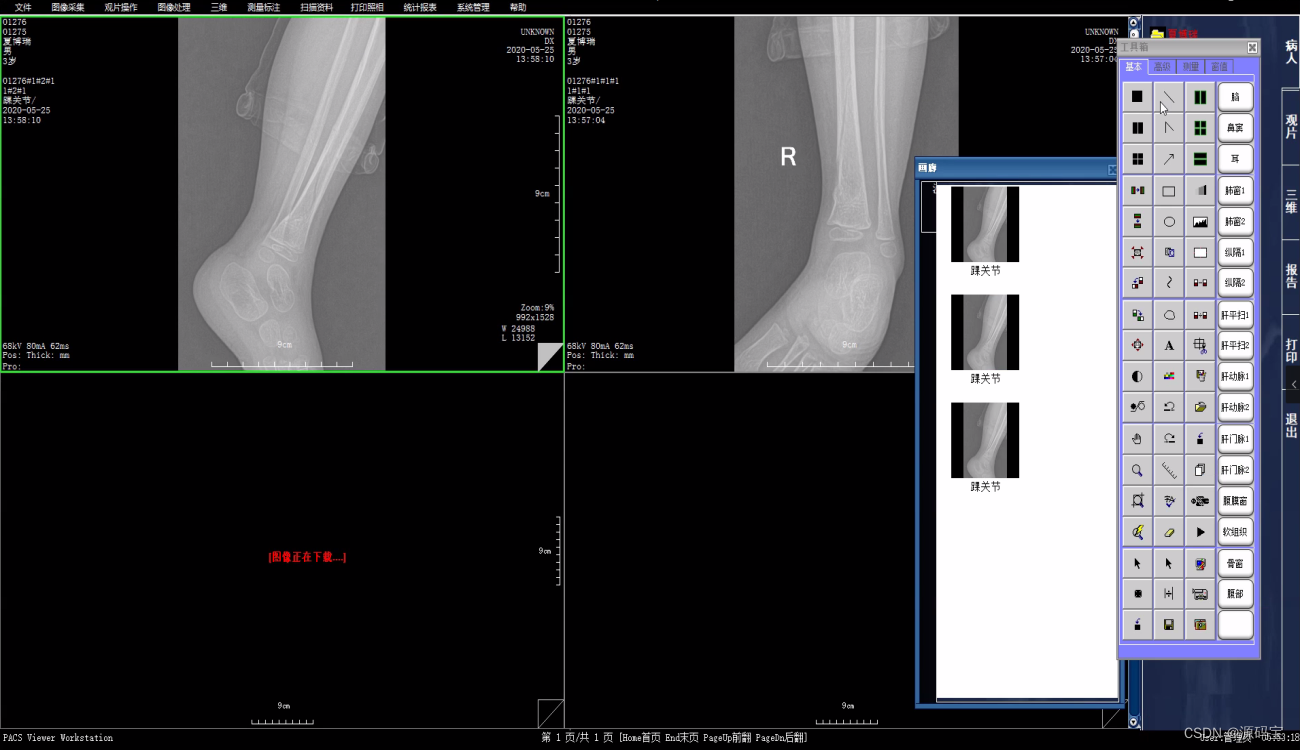

PACS系统可实现检查预约、病人信息登记、计算机阅片、电子报告书写、胶片打印、数据备份等一系列满足影像科室日常工作的功能。

全面PACS/RIS,实现对不同设备、不同图像信息的处理。

多种临床工具包,可对图像进行多种增强处理、测量、标注,充分发挥电子胶片的特点。

(5)影像处理

同屏分格显示病人不同体位、不同设备的影像,供诊断比较;

影像漫游、无级缩放、局部放大;CT值坐标方式显示;

提供图像标注,角度、面积等测量,支持骨密度测量;

提供胶片打印功能,多种影像排列和影像组合方式输出。